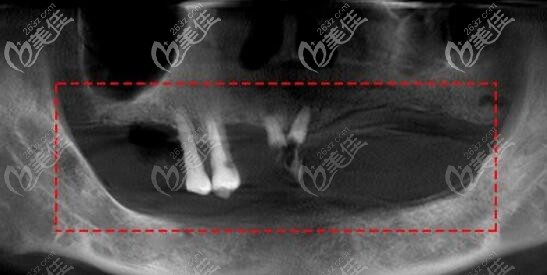

長時間缺牙后牙槽的骨吸收情況:

有的牙槽骨吸收比較多的顧客還要行植骨,才能骨量的充足,提高種植牙的。